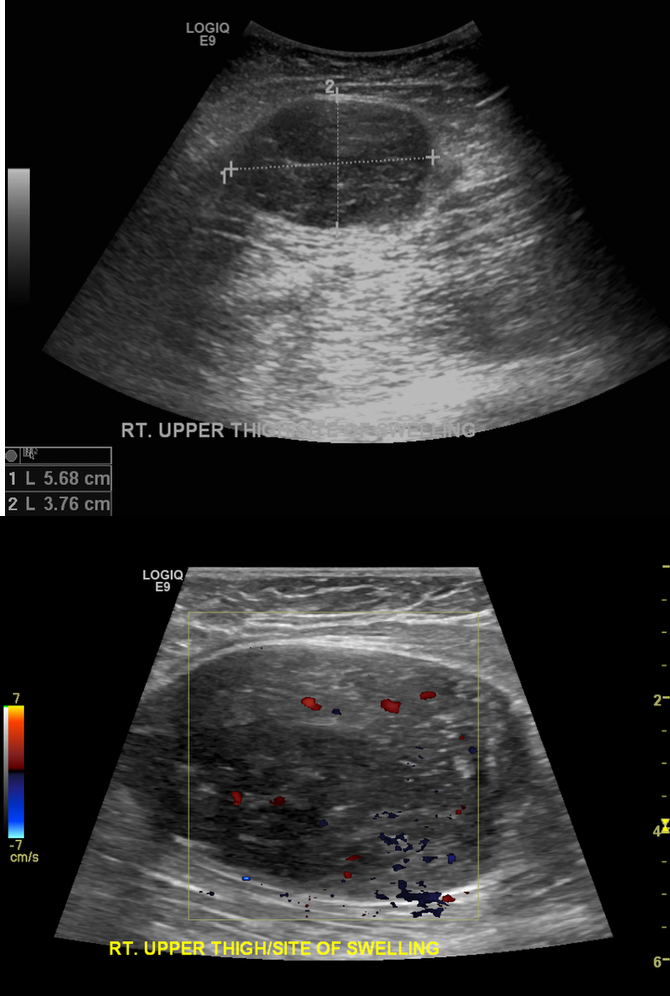

Which of the following matches with the findings below?

neoplastic IVC obstruction